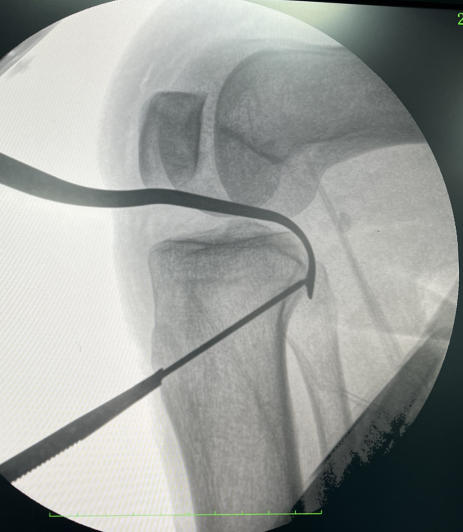

骨伤中心关节-运动科徐驰主任带领团队经过充分的术前准备,由刘志强、冯超医生择期为李女士在关节镜下行左膝关节镜下前、后交叉韧带重建+内侧副韧带修复+半月板修整成形术。

▲术中精细操作,重建膝关节功能

手术过程顺利,术后患者恢复良好,膝关节功能明显改善,膝关节稳定完全恢复,同时微创术后患者恢复快,术后第二天就能指导患者进行屈伸活动、肌肉力量等方面康复训练,手术取得了满意的效果。